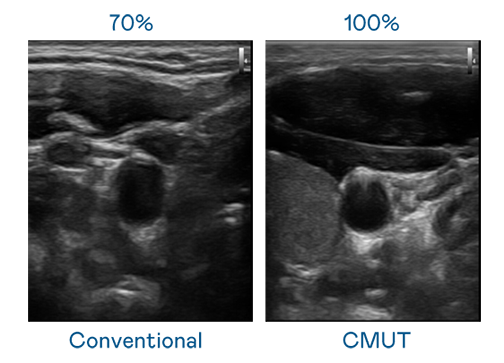

CMUT 技术是一种用电容式微机电元件来产生超音波讯号的技术。与传统 PZT 压电式技术相比,CMUT 频宽增加 30%,更宽频的超音波讯号让影像解析度大幅提升,是实现高影像品质医疗超音波扫描、促进精准医疗发展的关键技术。

大频宽带来超清晰影像

超音波影像的解析度高低,首先取决于探头能发出的讯号频宽。AG亚游集团 CMUT 可提供高清晰的超音波讯号,提供高频宽、高灵敏度、影像纹理细节更高的超音波影像,协助医护人员缩短影像判读时间及利用精准的医疗影像进行诊断。